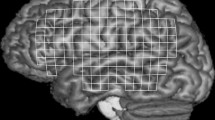

It could be ascertained by camera monitoring that all the subjects performed the lip protrusion task perfectly and symmetrically. The BOLD signals data analysis with Brain Voyager showed that the sensorimotor cortex was activated strongly and widely in all the subjects. No significant activation in Broca’s or Wernicke’s areas was observed. Table 1 shows the summary of the number of activated voxels in the sensorimotor cortex at a corrected P < 0.001 by the multiple comparison method, and the Talairach coordinates at the most active regions. In men, the results of individual data analysis revealed a larger number of activated voxels in the left sensorimotor cortex than that in the right, and there was a statistically significant difference in the number of activated voxels between in the left and the right side (Wilcoxon signed rank test, P = 0.0051) (Fig. 1). On the other hand, no significant difference was found between the left and right side in women (Fig. 2). There was a statistically significant difference in interaction between the hemisphere and sex (Two-factor factorial ANOVA, P = 0.041) and multiple comparison test showed statistically significant differences between “men and right” and “men and left”, and between “men and left” and “women and left” (Fisher’s PLSD method, P = 0.018, 0.026, respectively). The results of group data analyses indicated bilateral strong activation of the sensorimotor cortex during lip protrusion at an uncorrected P < 3.1294 e−12 level (corrected P-values could not be seen in the statistical maps; i.e, P < 0.000) by the multiple comparison method (Bonferroni’s correction) (Figs. 3 and 4). In general, the cluster size of the activated area in the group data analysis was larger than that in the individual data analysis because of the averaging of each individual data set. The areas of activation on the left side were larger than those on the right side in men, though no significant laterality was observed in women. Activation in the bilateral supplementary motor cortex and cerebellum was also observed, but no laterality was found (Wilcoxon signed rank test, P > 0.05, respectively). Detailed analysis of the averaged time-course of changes in the BOLD responses for the ROIs in the sensorimotor cortex revealed that the peak %BOLD signal in the left sensorimotor cortex was approximately twice as large as that in the right in the male group (Fig. 3), although no laterality was found in the female group (Fig. 4). In detail, the peak value of the percent changes in BOLD signals for the right sensorimotor cortex was approximately 0.5, whereas it was 1.2 for the left in men. In a GLM (multi-study, multi-subject) analysis, the left primary sensory area was significantly activated (yellow), though the right one was not activated (right, Fig. 5). A cluster center of spatial gravity was evaluated at the Talairach coordinate sets (−51, −22, 36) corresponding to the primary sensory area related to the face area. On the other hand, green regions were also activated as brain regions where female activation was greater than male. A cluster center of the left hemisphere green region near the yellow one was evaluated at the Talairach coordinate sets (−40, −21, 42) and that of the right one was (47, −19, 44). Statistical analysis of data in the group study and the male and female characteristics (mean age, laterality quotient, past history of facial nerve diseases or cerebrovascular diseases) are shown in Table 2. There was no statistically significant difference in the R/L amplitude ratio of the facial muscle action potential between men and women as shown in Table 2.

Contrast activation maps overlaid on coronal images in a GLM (multi-study, multi-subject) analysis. A “yellow” region shows a contrast asking for those brain regions where male is more active than female. The left primary sensory area is significantly activated (right, yellow). The “green” regions indicate brain areas where female activation is greater than male. The primary sensorimotor areas are almost symmetrically activated

Lip protrusion requires bilateral coordinated movements of the facial muscles, which are controlled by the cerebral sensorimotor cortex via the corticobulbar tract. Although a digital video study showed mild asymmetry of lip movement in voluntary puckering (Schmidt et al. 2005), it has been reported that the lip protrusion task elicited high correlation values among all electrode pairs of the perioral quadrants in electromyographic recordings, suggesting coordinated equivalent activation of all the quadrants (Wohlert and Goffman 1994). Lip protrusion is a midline movement, and therefore probably involves an equivalent contribution from the cerebral sensorimotor cortex of both sides. An electroencephalographic (EEG) study reported that non-speech movement of a midline structure was under bilateral cortical control, and that control of lip movement was apparently not necessarily a dominant hemisphere function (Wohlert and Larson 1991). Salmelin et al. also reported in an MEG study that no interhemispheric correlations were found for the non-verbal mouth movements (Salmelin and Sams 2002). As regarding fMRI studies, some authors showed no lateralization to the left hemisphere during articulation or swallowing with lip movements in healthy subjects (Kern et al. 2001; Lotze et al. 2000; Riecker et al. 2000; Wohlert 1993). These reports suggest that oral movements in the midline involve coordinated equivalent responses of the facial muscles under the control of the primary sensorimotor cortex of both sides. On the other hand, Kimura and Watson (1989) hypothesized that systems of neural control for all movements of the hand and mouth developed under a pattern of hemispheric dominance because both these parts of the body require coordination of many muscles for fine voluntary actions. Higashino et al. reported from an MEG study that voluntary lip movements without speech were controlled mainly by the left motor cortex (Higashino et al. 2002). Hesselmann et al. showed in an fMRI study that the left-sided lateralization for lip motor activity was established in the context of the group analysis, although it could not be proven within the scope of the single subject analysis (Hesselmann et al. 2004). Thus, the symmetry of the sensorimotor cortex activation during lip movements has been controversial. In the present study, the mean number of activated voxels and the magnitude of the BOLD signal responses in the left sensorimotor cortex were higher than those in the right in men, but this was not the case in women. In addition, a multiple comparison test revealed a statistically significant difference associated with hemisphere and sex. The left primary sensory area related to the face area was significantly activated as a region where male was more active than female in a GLM (multi-study, multi-subject) analysis. On the other hand, the anatomical localizations of the “green” clusters at the sensorimotor areas, as brain regions where female was more active than male, were almost symmetric in Fig. 5. These localizations were similar to those of the Hesselmann study as stated in the Sect. “Material and Methods”. This activation can account for primary sensorimotor activation within Brodmanns areas 4 (M1) and 1, 2, and 3 (S1) (Hesselmann et al. 2004). Although it is not clear why the localization of the activated voxels differed between men and women, it is interesting that the activation of the left sensory area was observed alone as a region where male was more active than female. These findings suggest that the laterality to the left of the function of the sensory cortex during lip protrusion may be associated with sex-related differences. To the best of our knowledge, ours is the first study to reveal the dominance of the left sensory cortex during non-verbal lip protrusion in healthy right-handed men with 3-tesla fMRI study. At the same time, for group data analysis, a random effects analysis should be performed in order to generalize the obtained fMRI results to the population level. However, 50 or more subjects per experimental group have to be included for a random effects analysis and so that analysis is not thought to be very informative for our study.